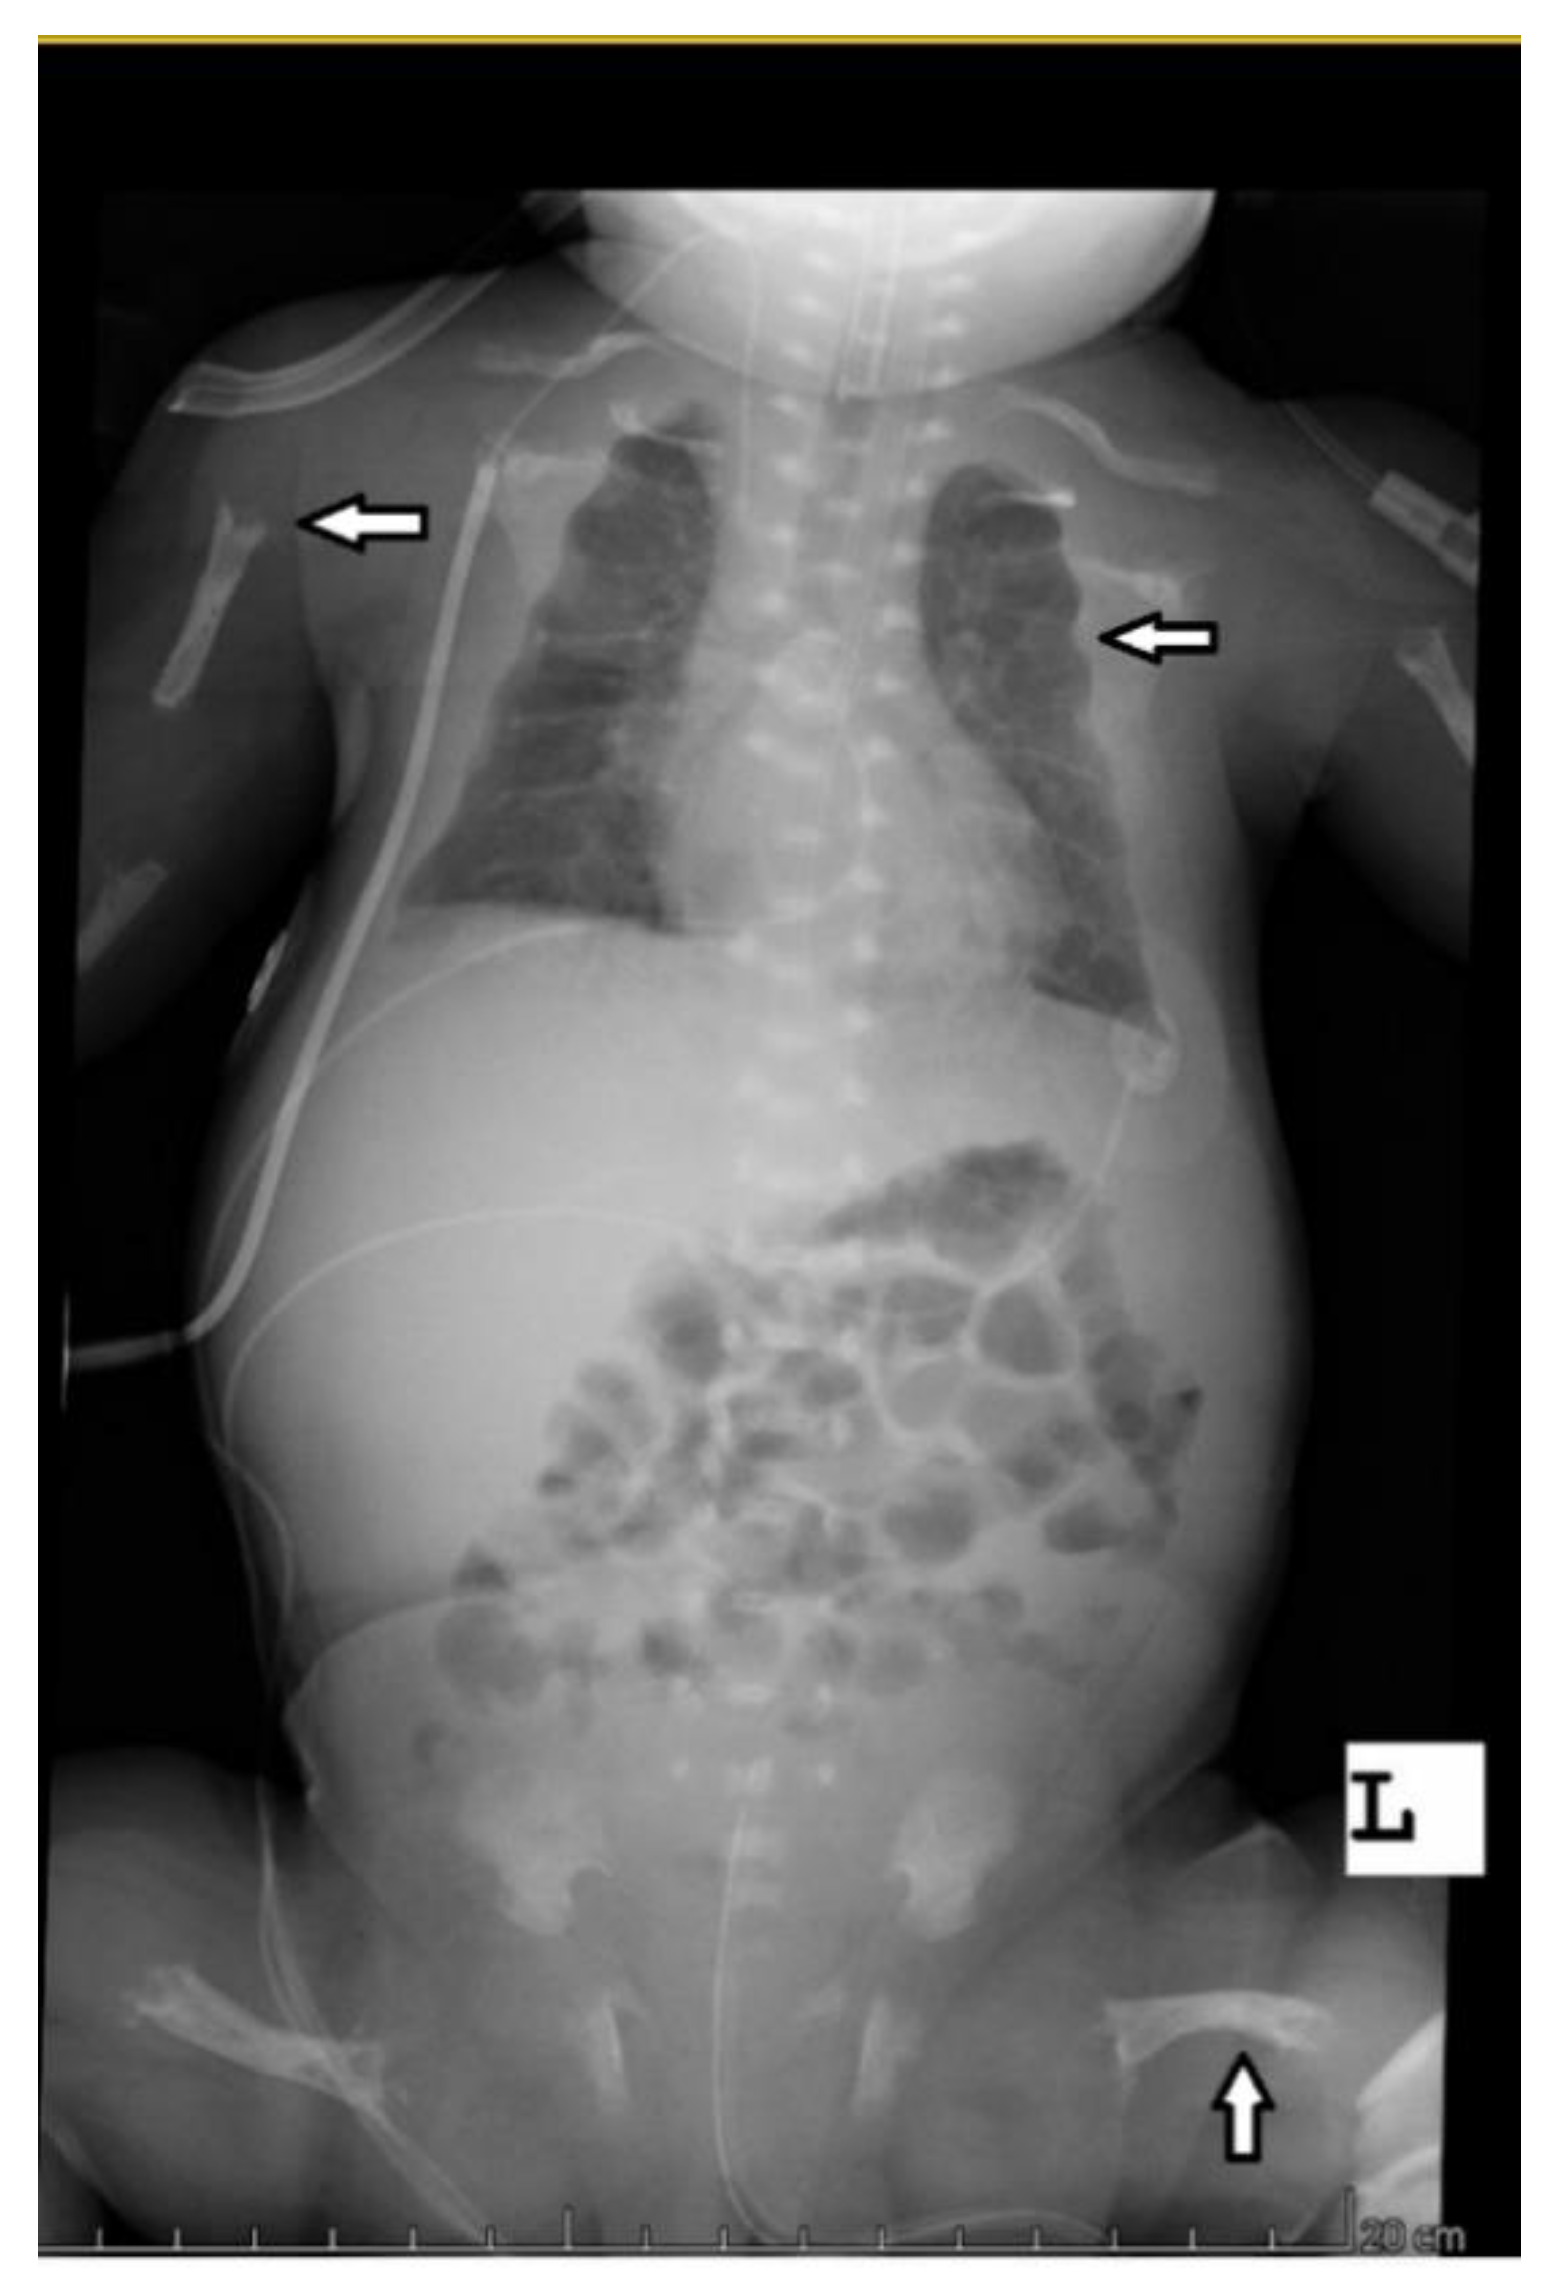

The abdominal ultrasound examinations showed the features of urolithiasis in 3/16 patients, and the X-ray examinations revealed the most common disorders of bone mineralization, abnormalities in the epiphysis of long bones–dilatation, uneven contours, bone defects, and fractures (Figure 1 and Figure 2).

Bone structure abnormalities observed in X-ray were characteristic and most severe for the perinatal and infantile types (they occurred in all the patients of these groups), while in other HPP types, they occurred much less frequently. A decrease in bone mineral density, assessed by densitometry, was observed in the infantile and childhood types, but it should be noted that bone demineralization was described in the perinatal type on bone radiography. In this case, DXA was not performed due to the severe patient’s condition.

Figure 1. Babygram of a patient with the perinatal disease type—disturbances in bone mineralization, bone structure, uneven edges of the epiphyses, and bone deformities after fractures.